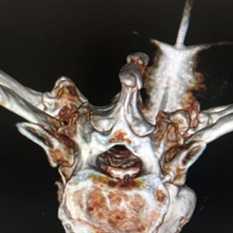

(Слева) КТ, аксиальная проекция, костный режим: случайно выявленный в крестце костный островок. Однородный склеротический очаг имеет типичные признаки угасания на периферии с переходом в сопряженную кость. Это может давать характерный несколько инфильтративный вид щетки или звездчатость.

(Справа) Рентгенография в ПЗ проекции: типичный пример костного островка в позвонке. В данной проекции патологический очаг прилежит к ножке дуги позвонка. Другие характерные признаки отсутствуют. (Слева) КТ, аксиальная проекция, костный режим, выполнена для более точной оценки патологического очага у этого же пациента: определяется плотный склерозированный очаг сумеречно заостренными периферическими краями.

(Справа) КТ, сагиттальная проекция, костный режим с переформатированием: подтверждается наличие плотного склерозированного костного островка с неровными щетко-образными краями. Также обратите внимание на то, что патологический очаг расположен вдоль длинной оси тела позвонка. Костный островок может иметь округлую или овальную форму. В этом случае это единственно возможный обоснованный диагноз. (Слева) МРТ, сагиттальная проекция, режим STIR: небольшая отчетливо визуализирующаяся зона сигнала низкой интенсивности в теле позвонка. Сигнал сохраняет низкую интенсивность во всех последовательностях. Обратите внимание на отсутствие в режиме STIR перифокального отека или реактивных изменений.